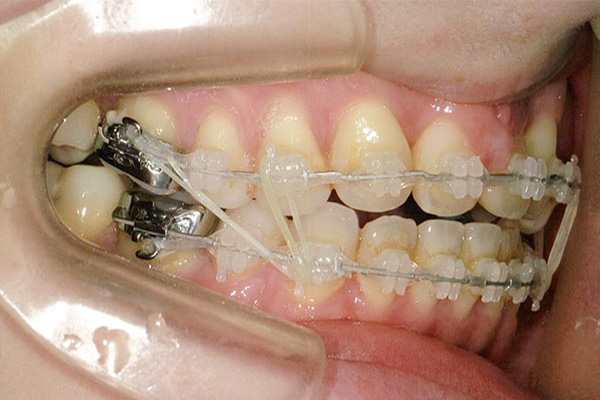

1年6ヶ月後